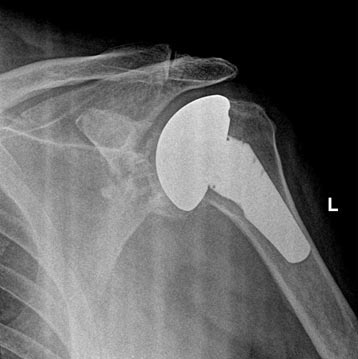

Total Shoulder Replacement With Metal Ball and Plastic Socket